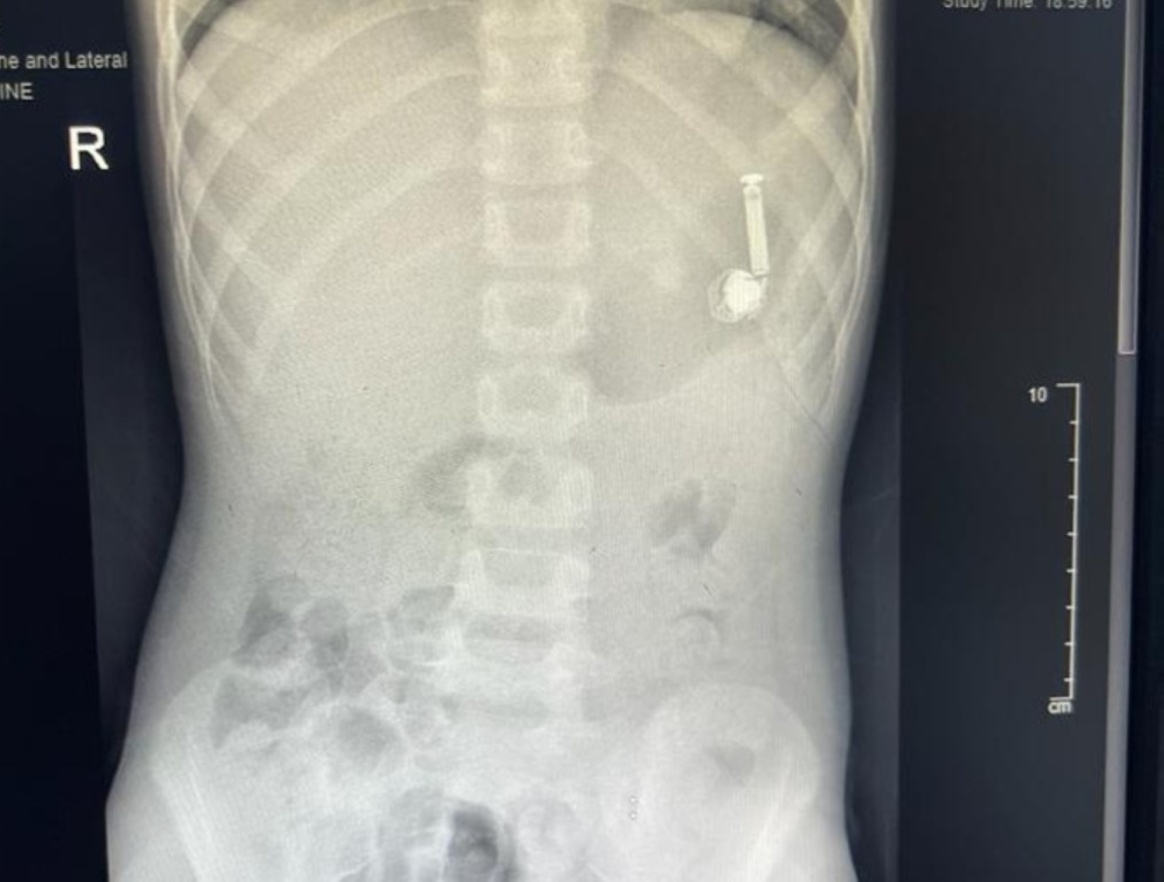

نجح فريق طبي بمستشفى الولادة والأطفال عضو تجمع مكة المكرمة الصحي، في إخراج سماعة جوال من داخل جوف طفل يبلغ 10 سنوات، ابتلعها نتيجة رفض والدته إعطاءه جهاز الجوال.

وذكر المستشفى أن الحالة وصلت لقسم الطوارئ بالمستشفى، حيث أخبر الأهل الطاقم الطبي أن ابنهم ابتلع السماعة، فيما جرى على الفور مناظرة الحالة وعمل الفحوصات الطبية اللازمة وشُكل فريق طبي من قسم المناظير وقسم التخدير للتعامل مع الحالة وتجهيز الطفل لعمل المنظار دون تدخل جراحي.

وأبان أن العملية تكللت بالنجاح في وقت قياسي، تم على إثرها إزالة السماعة والتأكد من صحة الطفل وقد غادر المستشفى وهو يتمتع بصحة جيدة.